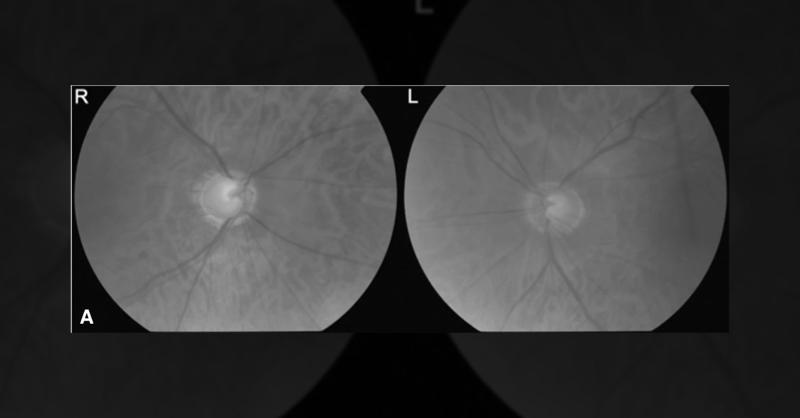

Abstract Neovascular glaucoma (NVG) is a vision-threatening secondary glaucoma caused by anterior segment neovascularization due to retinal ischemia. We report a case of NVG secondary to ischemic central retinal vein occlusion (CRVO), emphasizing early diagnosis and multimodal management. Introduction Neovascular glaucoma is commonly associated wit

PRESENTATION 30-year-old male Medical history of fever for about 2 weeks. After the flu subsided, the patient felt pain in the eyes during eye movement. He visited an ophthalmologist in another clinic for evaluation, and eye drops were given. On day 5, he developed blurry and decreased vision and visited Aster for re-evaluation. He was seen by an O